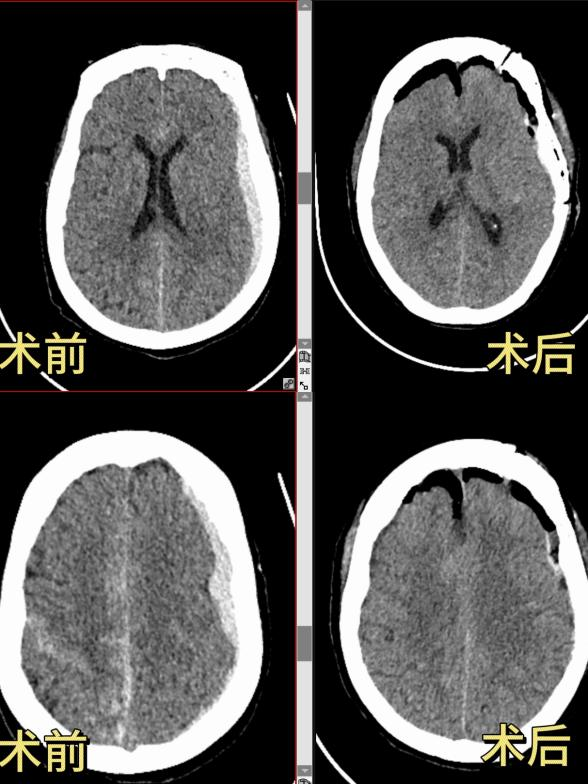

神经外科团队凭借扎实的专业功底、成熟的手术经验,精心设计最优手术方案,果断为患者实施高难度开颅手术。术中精准定位、精细操作,一次手术同步完成动脉瘤夹闭与硬膜下血肿清除,

一次性解决两大致命问题,彻底清除颅内所有隐患,手术成功。

在科室医护团队的精心治疗与专业护理下,黄奶奶闯过术后重重难关,意识逐渐清醒,生命体征平稳恢复,肢体功能、生活能力逐步改善,目前,已顺利康复出院。